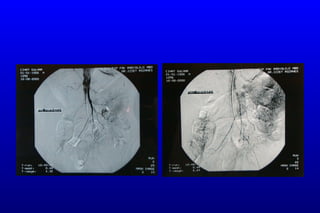

Hastaya  anjiografi yapıldı. SMA total oklüde / çölyak trunkusta %90-95 darlık saptandı. Çölyak trunkustaki darlığa stent uygulandı.

Süperior mezenterik arter Çölyak trunkus

Çölyak trunkusa stent sonrası

Hastaya anjiografiyapıldı. SMA total oklüde / çölyak trunkusta %90-95 darlık saptandı. Çölyak trunkustaki darlığa stent uygulandı.